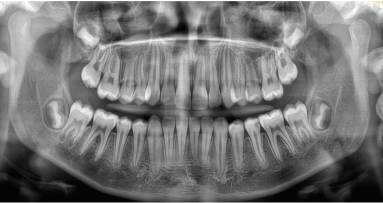

Nowoczesna implantologia nie może istnieć bez precyzyjnej diagnostyki. Prawidłowe rozpoznanie warunków anatomicznych pacjenta to podstawa skutecznego i bezpiecznego leczenia. Dzięki zaawansowanym technologiom obrazowania 2D i 3D lekarz ma możliwość dokładnej oceny ilości i jakości kości, przebiegu nerwów, zatok szczękowych oraz innych struktur anatomicznych. Obrazowanie cyfrowe pozwala nie tylko minimalizować ryzyko powikłań, ale również planować zabiegi implantologiczne z najwyższą dokładnością, a tym samym zwiększać przewidywalność i komfort terapii.